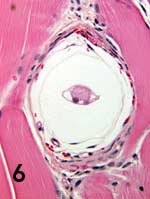

Merogony occurs in tissues of the canine host (Figure 6A, H americanum; Figure 6B, H canis). Released merozoites provoke pyogranulomatous inflammation and vasculitis (Figure 7) that may lead to hypertrophic osteopathy (Figure 8) with ACH. Merozoites enter neutrophils to become gamonts.

Typical appearance of 2 Hepatozoon species meronts. (A) Early H americanum with onion skin appearance (magnification, 40×) and (B) early H canis with wheel-spoke appearance (magnification, 40×).